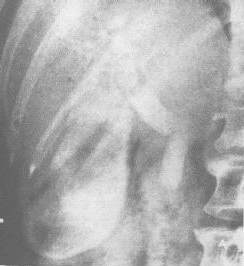

經皮肝穿刺膽管造影(percutaneous transhepatic cholangiography,PTC):使用帶塑膠管外鞘的穿刺針或Chiba細...

X線檢查雖然是膽道疾病診斷的常用方法,但有些病患在普通X線片上不能明確顯示,這就需要使用醫學造影劑經一定方法和渠道使之進入膽道,使膽道造影部位的輪廓及病...